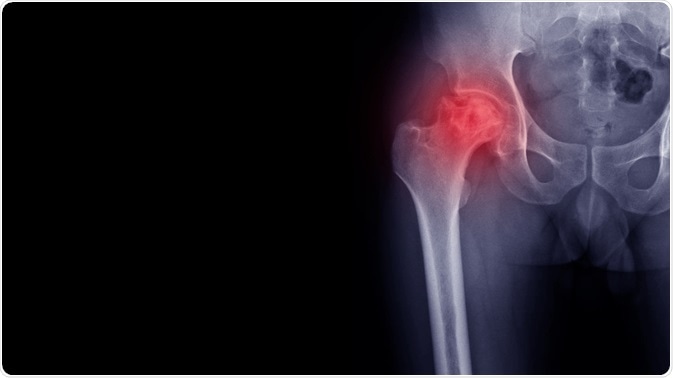

osteoarthritisImage Credit: joel bubble ben / Shutterstock.com